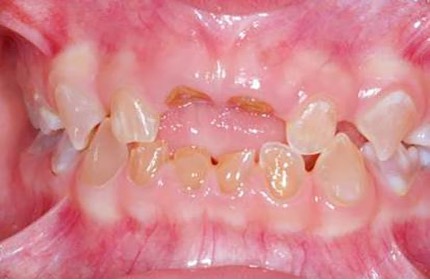

El examen clínico intraoral reveló alteración de la estructura y color de las piezas primarias, atrición y pérdida de la dimensión vertical (Figura 2). Radiográficamente se observó la presencia de coronas con marcada constricción cervical y raíces cortas (Figura 3). Presentaba alto riesgo cariogénico, por la presencia de lesiones de caries activas y dos restos radiculares, sumado a la anomalía estructural de la dentina (riesgo biológico específico) y bajo riesgo gingivoperiodontal. El riesgo socio-económico era alto por provenir de una familia con marcadas limitaciones económicas. Luego de la anamnesis, examen clínico y radiográfico, e interconsulta con el médico de cabecera se estableció el diagnóstico de DI Tipo I asociado a OI tipo I. Se planificó un tratamiento integral y preventivo con los objetivos de devolver forma y función, y proteger y evitar el desgaste de los tejidos conductas que pudieran interferir con el tratamiento.

Figura 2: Examen clínico intraoral del maxilar superior e inferior y vista anterior. Año 2007